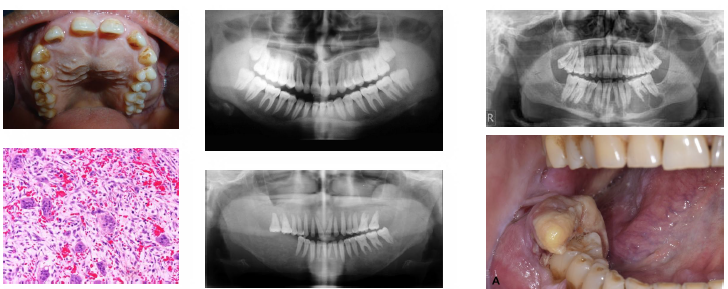

carcinoma of the maxillary sinus overview

•Malignant epithelial tumor of maxillary sinus

•Often squamous cell carcinoma histologically

•Associated with occupational and environmental exposures

•Frequently presents at advanced stage

•Close proximity to orbit and cranial structures

carcinoma of the maxillary sinus management and prognosis

• Requires combined surgical and oncologic therapy

• Radiation therapy commonly included in treatment

• Prognosis depends on stage at diagnosis

•Often poor due to delayed detection

Requires multidisciplinary management approach